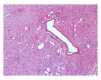

Neurofibroma is a benign peripheral nerve sheath tumor comprising variable mixture of Schwann cells, perineurial-like cells, and fibroblasts. Neurofibroma may occur as solitary lesion or as part of a generalised syndrome of neurofibromatosis or very rarely as multiple neurofibromas without any associated syndrome. There are two distinct variants of neurofibromatosis type I and type II. We present a case of neurofibroma of the hard palate associated with neurofibromatosis type I. The diagnosis of the lesion was made based on the clinical findings, family history, histopathology, and immunohistochemistry. Literature was reviewed and different types of neurofibroma, their incidence and frequency in the oral cavity, its association with neurofibromatosis, clinical manifestations, histopathologic characteristics, immunohistochemical analysis, behaviour, treatment, and recurrence are discussed.